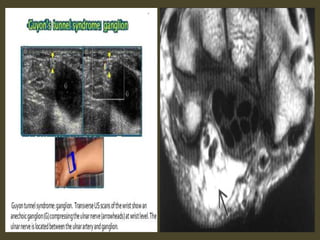

Ganglion cyst.